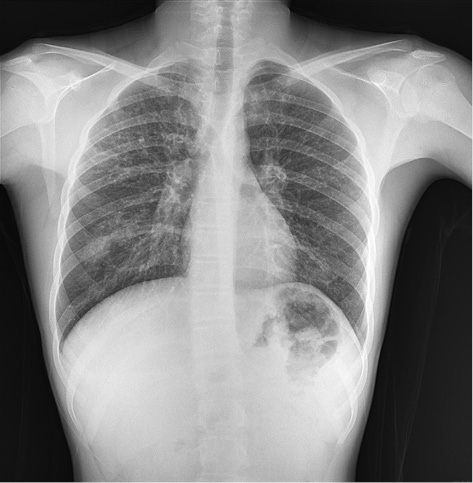

Figure 2. Villiform mucinous epithelial proliferation appears to replace the normal appendix mucosa

Pathologically, the appendix lumen diameter was 1.7 cm in the widest area. The appendix’s long axis was 7.5 cm. Mucoid material was observed in the lumen. The pathologic diagnosis was low-grade appendiceal mucinous neoplasm (appendiceal villous adenoma). Villiform mucinous epithelial proliferation was observed to replace the normal appendix mucosa [Figure 2]. It was observed that lymphoid tissue decreased In lamina propria and was replaced with fibrotic connective tissue [Figure 3]. Villiform mucinous epithelial proliferation appears to be composed of long mucinous epithelial cells with a low degree of nuclear atypia [Figure 4].